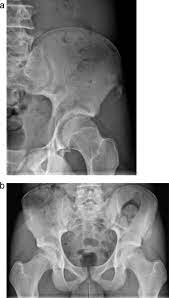

Signs Of Bone Cancer In Pelvis : Free Resources For Medical Professionals Bone Cancer Research Trust / Find out about the symptoms, causes, and treatment of chondrosarcoma, a type of bone cancer most common in your pelvis, thighbone, or upper arm.. It can spread to distant organs, such as the lungs. Pain in the affected bone is the most common sign of bone cancer. People with bone sarcoma may experience the following symptoms or signs. At first, the pain is not constant. Metastatic cancer can spread to any bone, but it most often spreads to bones in the middle of the body.

The amount of pain will vary from person to person. It can be found in the tissue outside the bone, though this is rare. The most common symptom of these cancers is bone pain or swelling in the pelvic area. Fsa tumors are found commonly around the skull, pelvis, spine and ribs. Bone pain may be hard to differentiate from ordinary low back pain or arthritis.

Bone cancer is rare, making up less than 1 percent of all cancers. Bone pain this is often the first and most common symptom. Pain, fever, and fatigue are all symptoms associated with pelvic bone cancer. Find out about the symptoms, causes, and treatment of chondrosarcoma, a type of bone cancer most common in your pelvis, thighbone, or upper arm. This is true of many different pelvic cancer symptoms and may include urinary incontinence, pain and feelings of fullness in the abdomen. Joint swelling and stiffness which may be the result of a tumor located near or in the joint a lump in the back of the throat if there is cancer in the bones of the neck. The usual treatment for bone cancer is surgery, and it has a good outlook. It can spread to distant organs, such as the lungs. In contrast, some other metastatic tumors, such as those from the prostate, are commonly osteoblastic, meaning that they form new bone and increase the brittleness of the bones. Acute lameness may be due to a bone fracture hard, obvious swelling over a long bone of a limb loss of appetite and significant weight loss Signs and symptoms of bone cancer. Symptoms of chondrosarcoma and osteosarcoma chondrosarcoma (cancer of the cartilage) and osteosarcoma (cancer of the bone) are cancers that occur most often in the pelvis, as well as the upper leg and shoulder. Rheumatic disease, arthritis or other conditions that affect the tendons surrounding the hip and the hip joint can also cause limping.

People with bone sarcoma may experience the following symptoms or signs. If bone metastasis affects your bone marrow, you may have other symptoms that are caused by lower blood cell counts. A few other early signs may include: Sometimes, people with bone sarcoma do not have any of these changes. When a bone tumor grows, it presses on healthy bone tissue and can destroy it, which causes the following symptoms: As the cells continue to lump together, the area within the bone swells, making it stiff and tender to touch. The most common symptom of these cancers is bone pain or swelling in the pelvic area. Joint swelling and stiffness which may be the result of a tumor located near or in the joint a lump in the back of the throat if there is cancer in the bones of the neck. It may be worse at night or when the bone is used, for instance, leg pain when walking. Pain in the affected bone is the most common sign of bone cancer. It can be found in the tissue outside the bone, though this is rare. Pain caused by bone cancer usually begins with a feeling of tenderness in the affected bone. Bone pain can cause a dull or deep ache in a bone or bone region (e.g., back, pelvis, legs, ribs, arms).

Cervical Cancer Signs Symptoms And Complications from www.verywellhealth.com Bone cancer can begin in any bone in the body, but it most commonly affects the pelvis or the long bones in the arms and legs. Bone pain is caused by stretching of the periosteum (thick membrane that covers bone) by the cancer, or by stimulation of nerves within the bone. Signs and symptoms of bone cancer. As the cells continue to lump together, the area within the bone swells, making it stiff and tender to touch. Bone pain this is often the first and most common symptom. If white blood cells are affected, you may get infections. At first, the pain is not constant. Osteosarcoma is probably the most common disease that is related to pelvic bone cancer, with chondrosarcoma following close behind it.